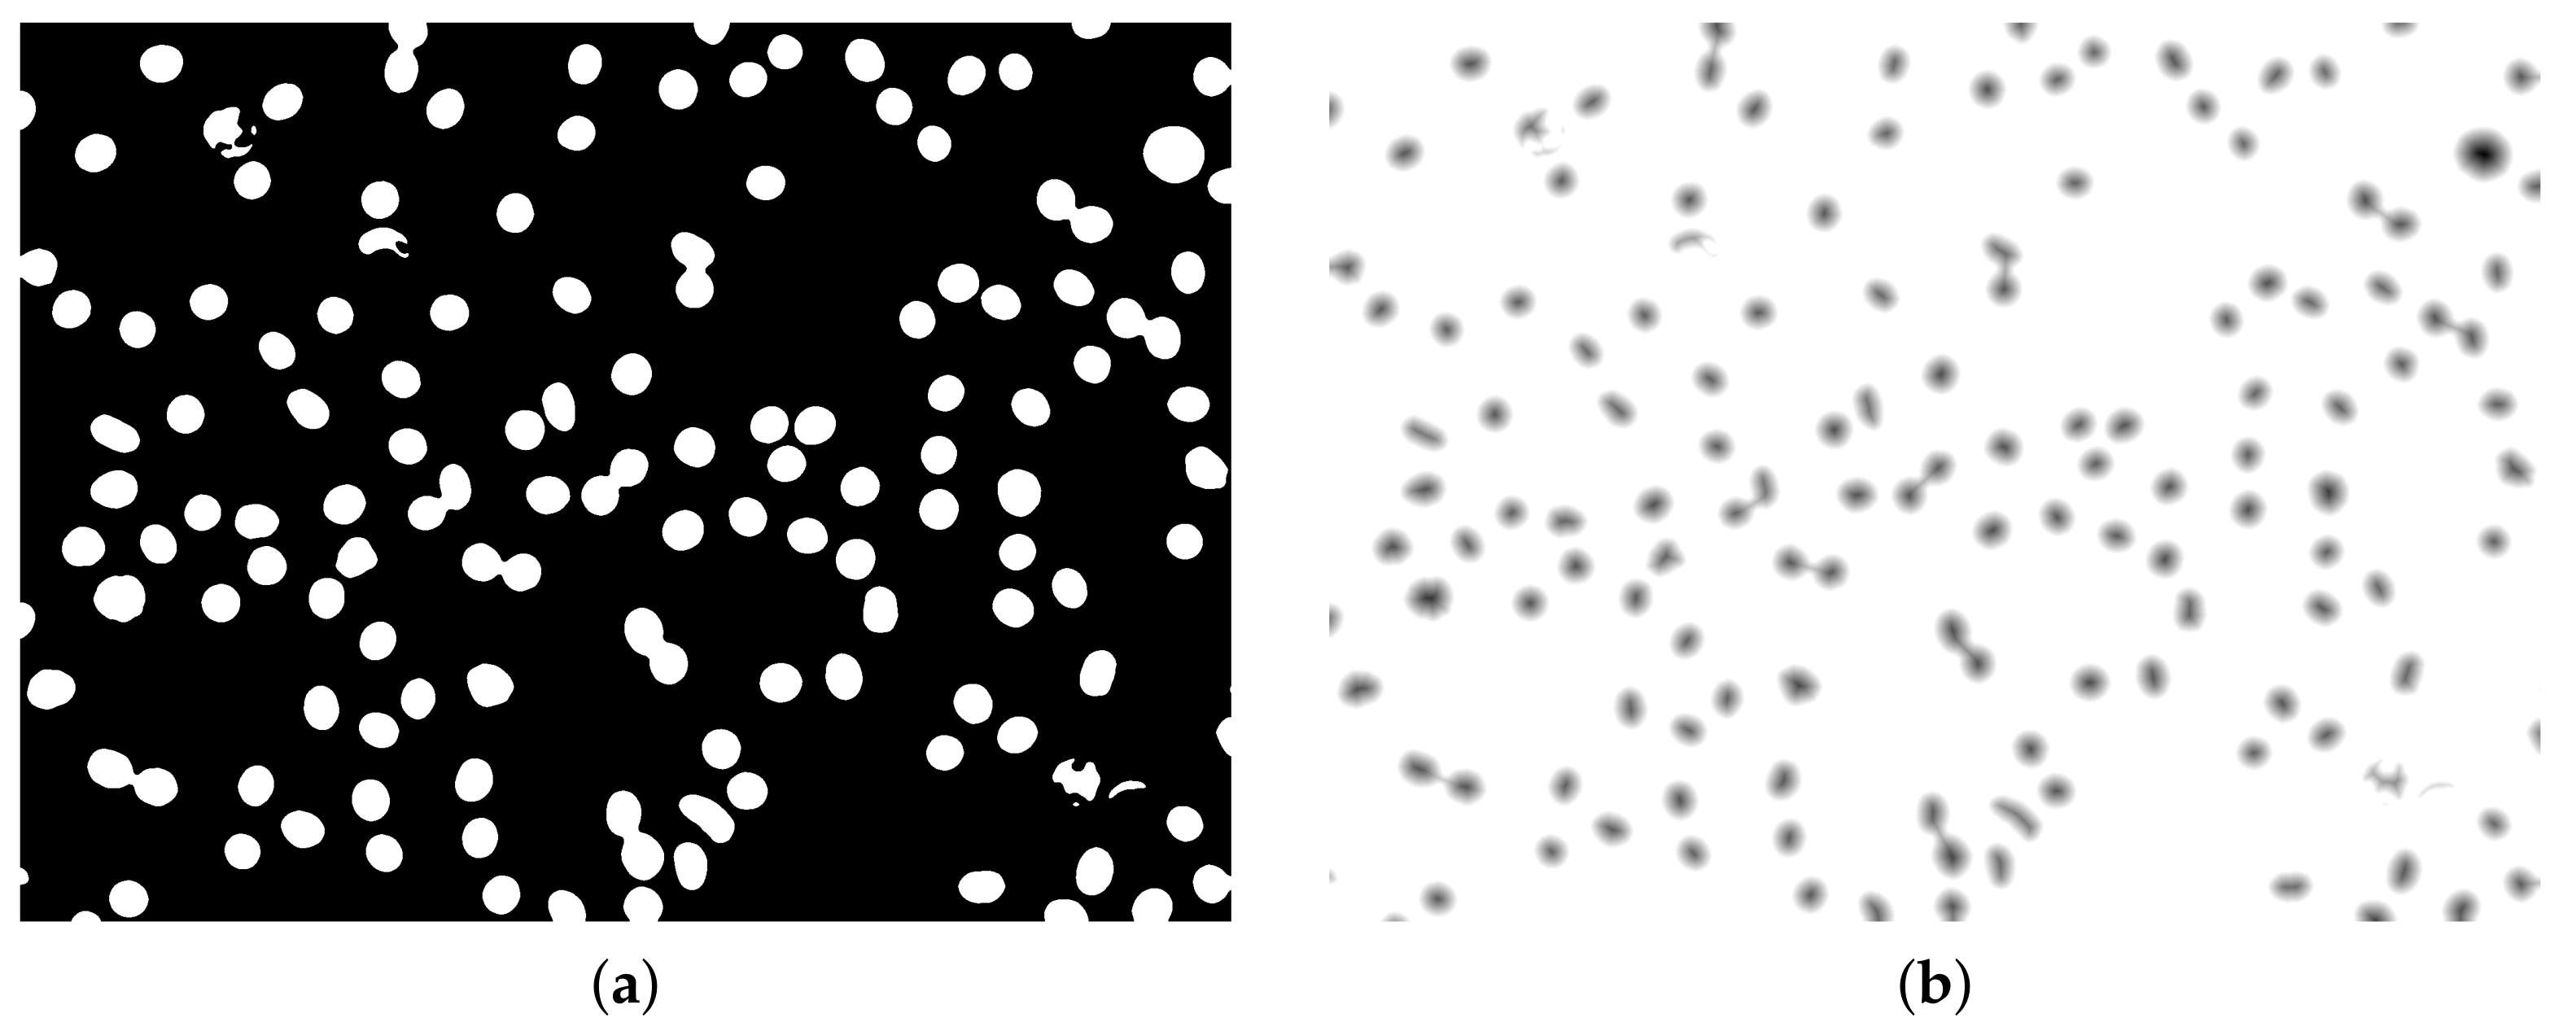

2.3. Distance Map

3. The Proposed Methodology

3.1. Initial Processing and Segmentation